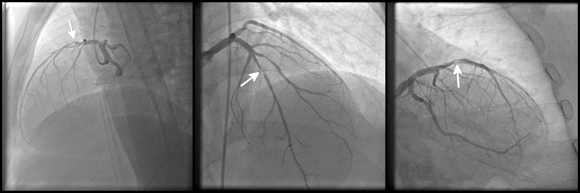

أيّ علامة إضافيّة في الصّورة بخلاف العيّنة أو الصّورة الطّبّيّة نفسها – قد تؤدّي إلى تدريب مغالط للخوارزميّة. صورة تصويريّة لمرض القلب التّاجيّ | kalewa, Shutterstock